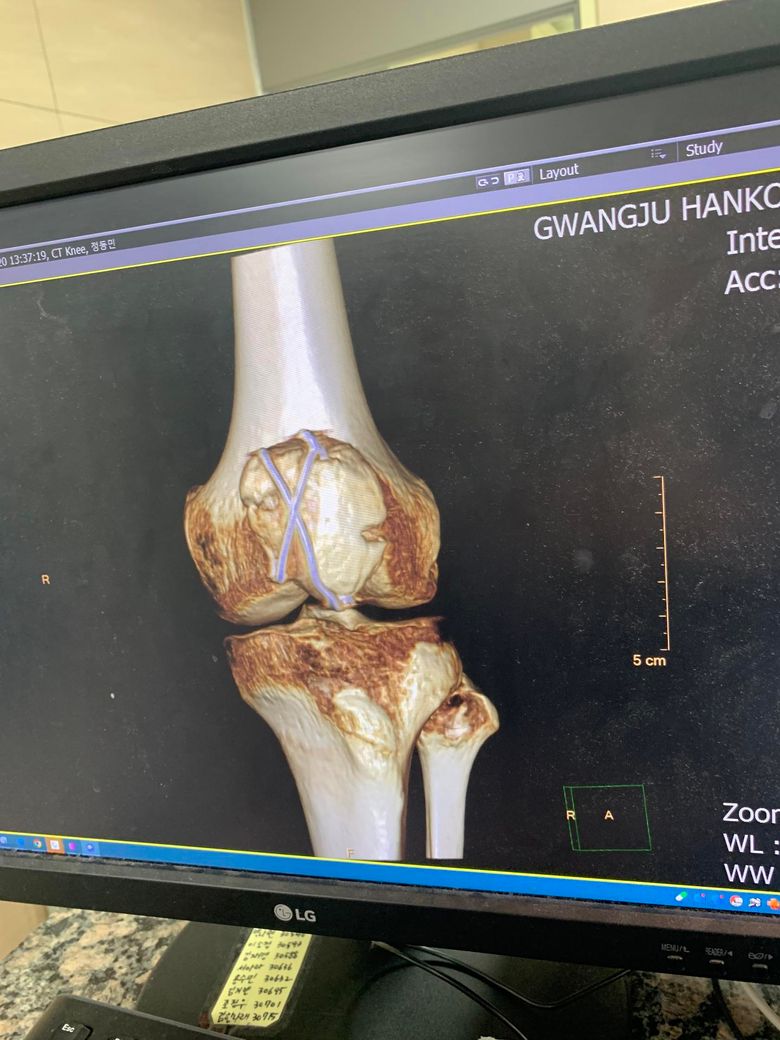

작년 6월초 슬개골 분쇄골절로 핀과 와이어를박았습니다

다만 사진은 핀제거전 ct사진인데 한쪽면이 뼈조각이

깨져서 날라갔다고하더군요 이건 기능상 문제가없는건가요? 재골절의 위험있을까봐 걱정됩니다

• 1번 째 사진

CT에서 보이는 한쪽 슬개골 조각 소실이 있어도 대부분 기능에는 큰 문제 없는 경우가 많고, 핀 제거까지 7개월 이상 유지했다면 재골절 위험은 높지 않은 편입니다. 슬개골은 완벽한 모양보다 힘줄(대퇴사두근–슬개건)이 잘 이어져 있고, 무릎을 펴는 기능이 유지되는지가 더 중요해요.